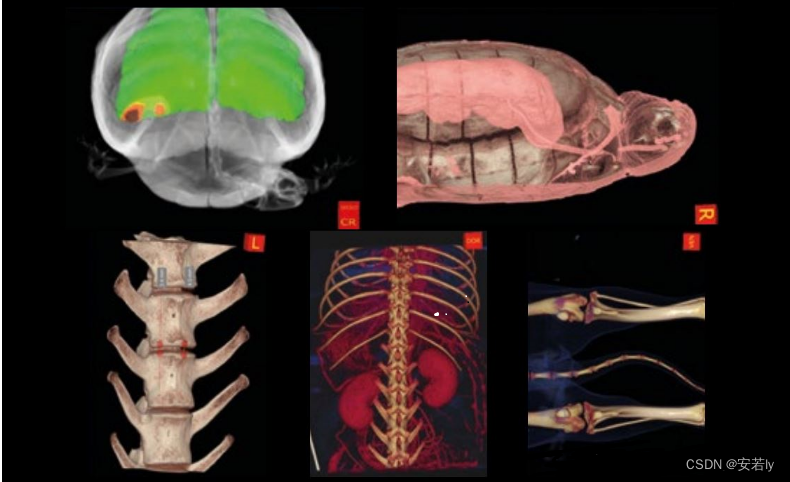

NNT软件的先进功能可以覆盖多个医学专业,特殊的重建窗口响应每个部门的不同需求。所有检查都完全兼容 DICOM 格式:它们可以通过 NNT 查看器共享或以 1:1 的比例打印。与 NewTom 采用的现代系统的出色连接性和集成性。工作流程、临床和诊断活动变得更加容易和高效。简单的 3D 显示界面使与宠物主人的交流变得更加容易,即使是不熟悉影像阅读的观众也能清楚地了解患者的病情。可以选择软组织和骨组织的单独或叠加成像。3D 测量、气道模拟和切片工具也可用于获取感兴趣体积的横截面。用于研究牙弓的专用界面可生成横截面和轴向重建,并通过多平面重建生成与牙科全景图相当的图像。它还可以为冠状面和矢状面生成特定的重建。对于所有这些图像,可以独立管理厚度、亮度和对比度。NNT 软件有一个专门的窗口,用于骨骼结构的双边成像,例如颞下颌关节和较小的关节。观察窗在中间显示轴向图像,左侧和右侧显示专用重建;在底部中央区域,显示了 3D 效果图。